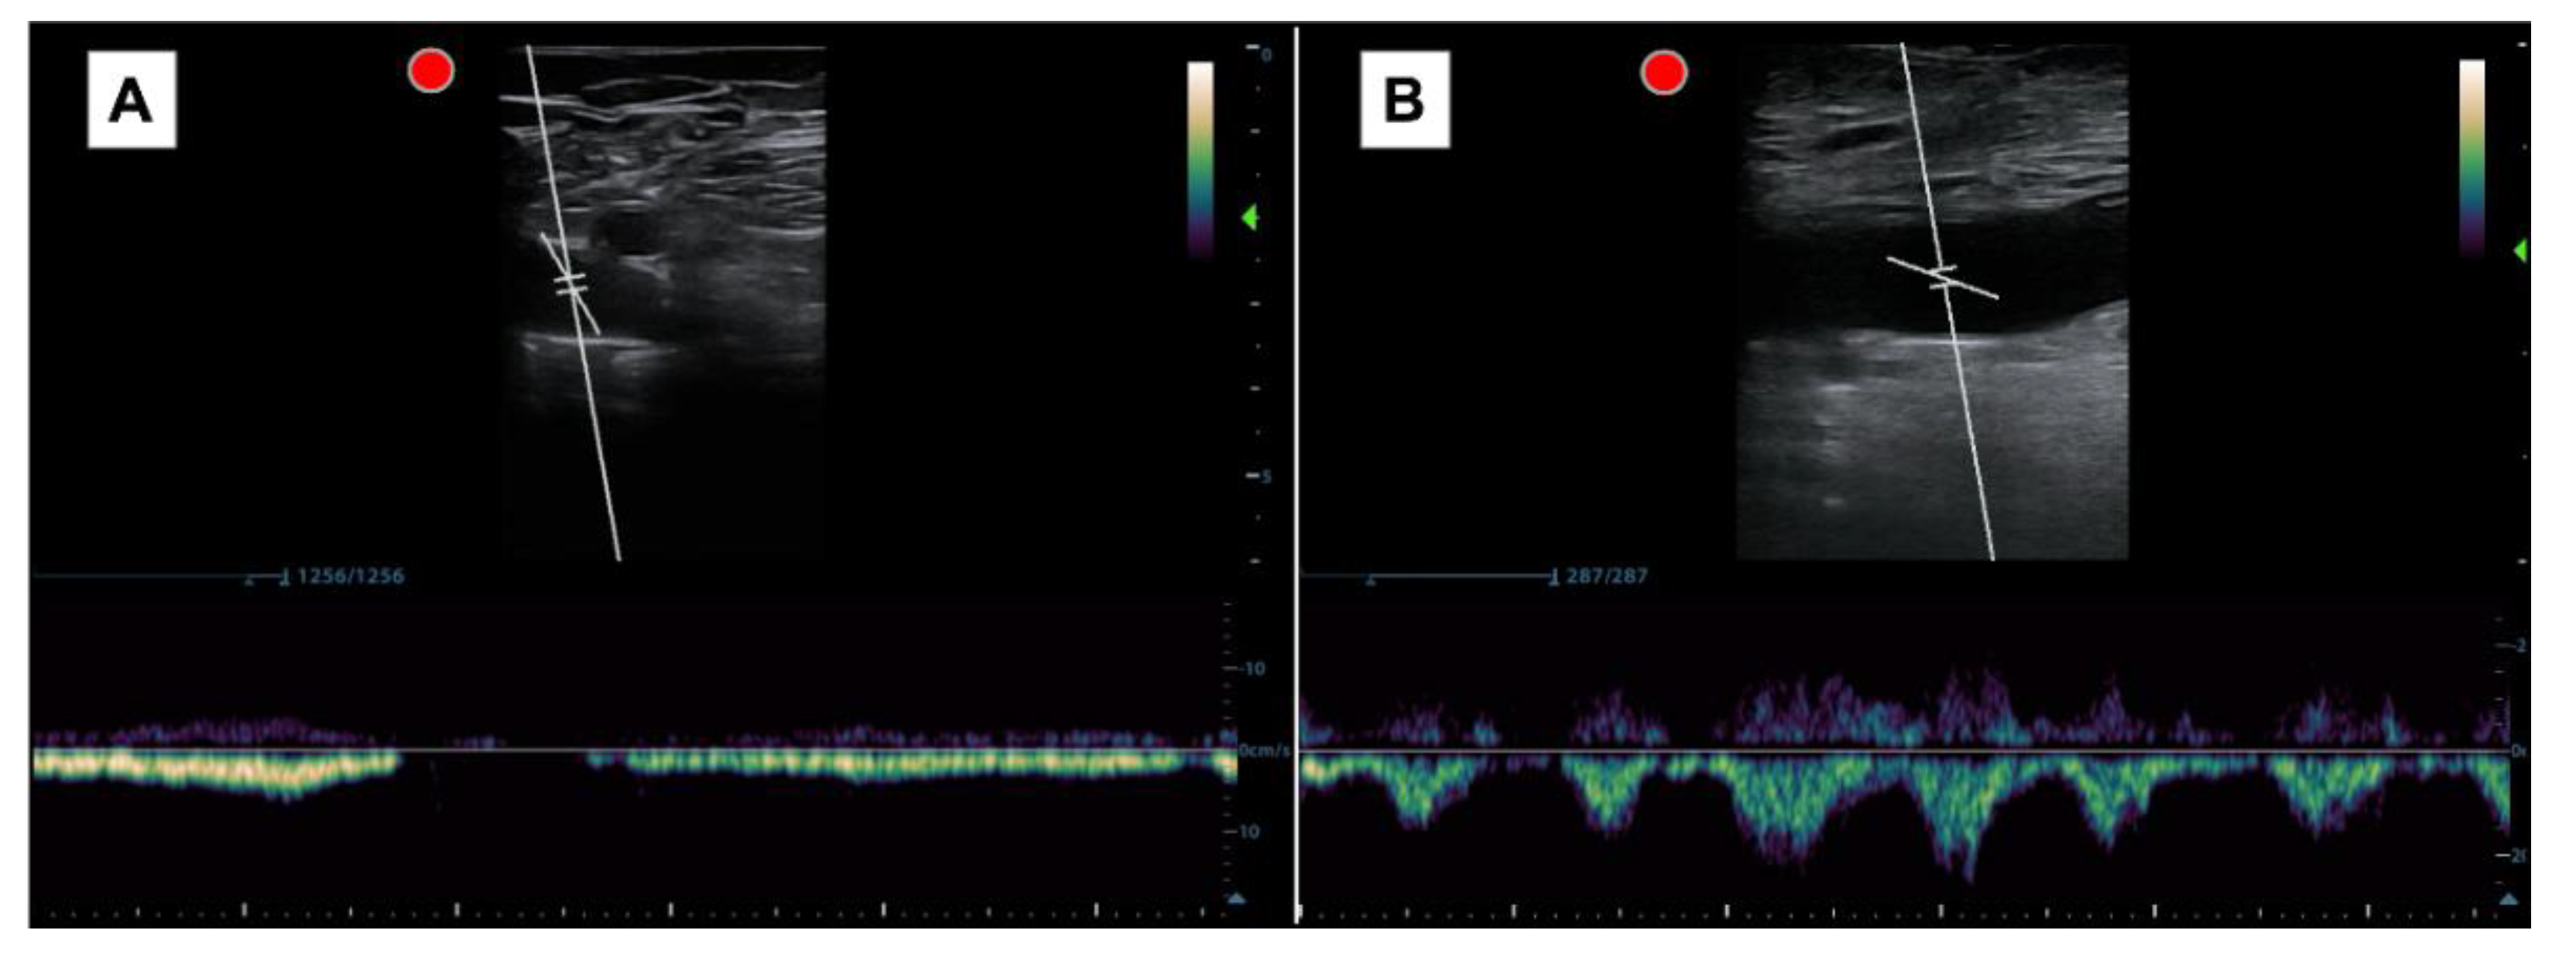

The pattern obtained was interpreted as either a respiratory (normal) or cardiac (pathological) pattern. The cardiac pattern is recognized when the systolic and diastolic waves are clearly identified, regardless of whether there is retrograde flow or no flow during spontaneous inspiration. The respiratory pattern, on the other hand, is defined when the systolic and diastolic waves are not adequately distinguished and disappear with inspiration (Figure 3).

When developing the study protocol, we faced difficulties in choosing how to conduct the examination. The first thing we considered was what we really wanted to assess. We must consider that, being a relatively new window, there was a lot of variability in the variables studied at the level of the PW-Doppler flow in the CFV. According to the authors, they valued: pulsatility, retrograde flow (with different speeds as cutoff points), respiratory phasicity, the pulsatility index, maximum or minimum speeds, or cardiac modulation. To choose the most optimal parameter, we took into account the interesting findings of Taute et al., who assessed the presence of cardiac modulation (which is equivalent to the cardiac pattern or pulsatility without respiratory phasicity) in 47 patients with acute pulmonary embolism, and observed that all patients with a right cardiac score of ≥1.75 had cardiac modulation (Sn 96%, Sp 88%) [8]; and our own preliminary findings; in which we observed that the pulsatile pattern in the PW-Doppler in the CFV reasonably detected elevated PHP (AUC 0.8, Sn 95%, Sp 64%, PPV 84%, NPV 84%) in 74 patients with heart failure [9]. In our previous study, we studied the role of pulsatility, retrograde flow (which may be present if the patient has venous insufficiency), and respiratory phasicity to establish which were the best variables. Bringing all this data together, we decided to distinguish only two patterns. The cardiac pattern, as one in which the cardiac waves are easily distinguished and in which breathing does not generate the absence of flow, and the respiratory pattern, in which the waves are not distinguished and with breathing, the flow disappears (Figure 3).

Figure 3. (A) Pulsed Doppler spectral waveform at the right CFV with a normal pattern of respiratory modulation. The flow is directed towards the heart in the expiratory phase and stops in the inspiratory phase. (B) Pulsed Doppler spectral waveform at the right CFV with an anormal pattern with cardiac modulation. Systolic and diastolic waves are clearly identified whether retrograde flow is present during spontaneous inspiration.